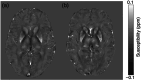

Methods: Thirty-two adults with ADHD (35 ± 10 years) and 29 age- and sex-matched controls (32 ± 12 years) underwent magnetic resonance imaging (MRI), standardized psychometric testing and assessment of lifestyle factors. Quantitative susceptibility mapping (QSM) was used to assess magnetic abnormalities indicating local alterations of iron deposition in the brain. By calculating QSM-maps, local iron deposition was tested for statistically significant differences between ADHD and healthy controls. Plasma neurofilament light chain (NfL) levels were measured as an indicator of neuroaxonal integrity by using a fourth-generation ELLA immunoassay.

Results: Brain iron content differed in persons with ADHD, with strongest effects observable in the right precentral cortex (healthy controls: 0.0033 ± 0.0017ppm; ADHD: 0.0048 ± 0.0016ppm; t(59) = 3.56, P < 0.001). Moreover, right precentral cortex iron in persons with ADHD was associated with increased blood NfL levels (F(1.57) = 13.2, P = 0.001, r2 = 0.19).